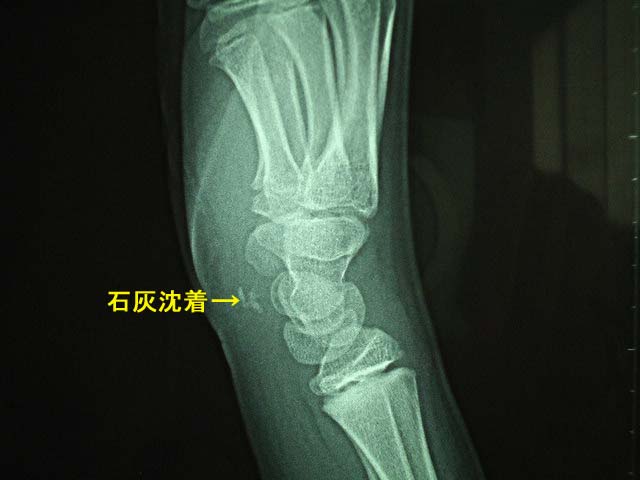

手部石灰沈着

手部の腱や靭帯、関節包の周囲に石灰物が沈着する疾患です。原因は不明です。中高齢者に多く認められ、症状として手関節や手指に激痛、脹れ、発赤(赤くなる状態)を認めます。

レントゲン検査で

手関節部手指に石灰物が確認できれば確定診断されます。稀に若年者にも発生することがありますので要注意です。なお痛風や偽痛風の鑑別が必要です。